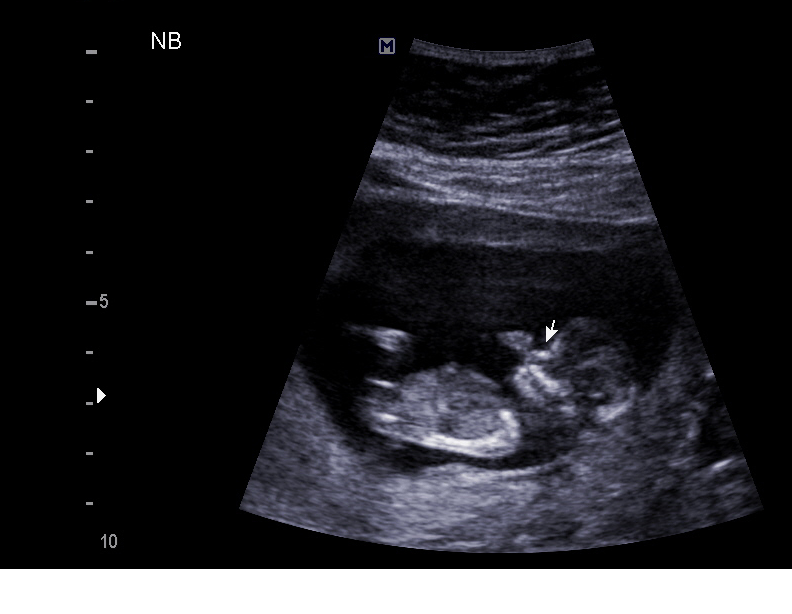

Just got back from my 12 week/NT scan appointment. Everything turned out wonderfully! It was the first time we'd heard the heartbeat and had the chance to see this baby! I'm measuring exactly as I thought ! 12w1d. NT measurements were 0.92 with a heart rate of 159. The baby was sleeping like a rock - the tech made me roll over onto my left side and then the baby finally moved around. Pic attached!